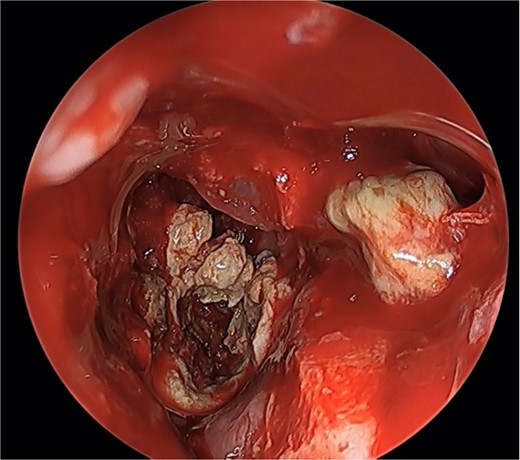

We present a case of a 52-year-old female, not known to have any chronic disease, who presented to our institution’s otorhinolaryngology clinic with a complaint of headache, facial pain, and PND for 6 months. Endonasal endoscopic examination was unremarkable. A paranasal sinus CT was requested to aid the diagnosis, which showed two simultaneous opacities occupying the left maxillary and right sphenoid sinuses, respectively (Fig. 1A and B). The opacified lesions were associated with calcifications, metallic shadowing, and bony thickening of the sinus wall. According to the history and radiological imaging findings, a diagnosis of a fungal ball occupying both the maxillary and sphenoid sinuses was achieved, and a functional endoscopic sinus surgery (FESS) with left wide maxillary antrostomy removal of the thick fungal debris occupying the left maxillary sinus (Fig. 2) was decided to be performed. In addition, a wide endoscopic sphenoidotomy was performed, and the sphenoid sinus was full of fungal debris (Fig. 3), which was cleaned thoroughly. The patient had an uneventful post-operative course.

Endoscopic view of simultaneous occurrence of the fungal ball in maxillary and sphenoid sinuses.